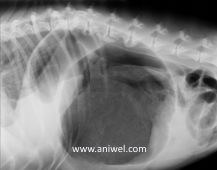

画像は胃捻転拡張症候群のワンちゃんのレントゲンです。拡張型心筋症にも罹患していて胸水も貯留していました。